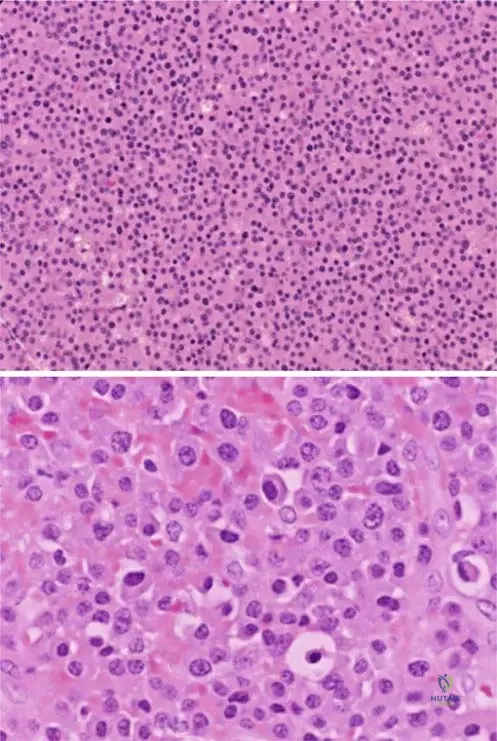

A 63-year-old female undergoes a bone marrow biopsy for suspected multiple myeloma. Microscopic examination of the biopsy reveals a characteristic cellularity and matrix production pattern. What is the typical description of myeloma lesions on low power photomicrography?

Correct Answer: C

Question 72

View Answer & Explanation

Rationale: Fig. 8.114 a, b's caption states, "Eccentric nuclei and prominent cytoplasm are evident on higher power (b). Myeloma cells are secretory and have well-developed golgi apparatus." This precisely describes the characteristic features of myeloma cells. The other options describe features of different cell types or tumors.